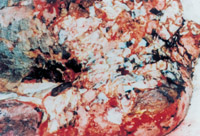

3-5 這是皮膚及皮下組織被切除后的創(chuàng)面情況,表現(xiàn)為深筋膜存在的肌肉層創(chuàng)面

3-6 處理結(jié)果:燒傷皮膚及未燒傷的皮下組織均被切除,胸部燒傷創(chuàng)面變成人為的外科手術(shù)切除的肌肉層創(chuàng)傷創(chuàng)面,已無任何燒傷組織及皮膚組織。